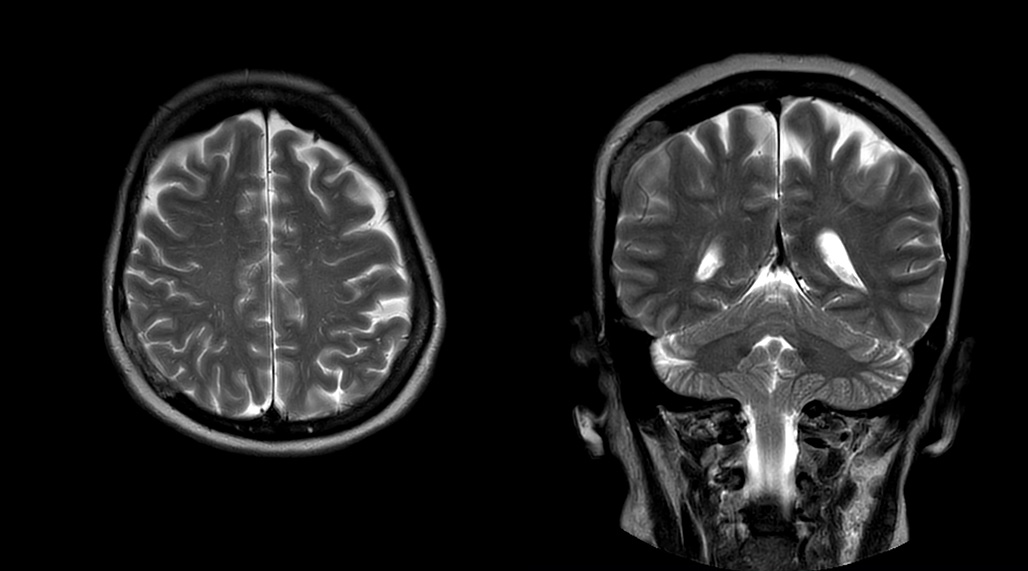

MultiVane XD helps eliminate motion for first-time-right scanning

DMG recognizes MultiVane XD motion compensation is another Philips technique that contributes to image quality and scan efficiency. “We run MultiVane XD for motion-free imaging on almost all our T2-weighted brain scans, just to reduce any repeats we might get. We know our non-contrast brain scans are going to take 20 minutes almost every time,” Mr. Duffy says.

“Using MultiVane XD still allows us to turn on dS SENSE, which significantly cuts scan time compared to what we were doing before,” he adds. “We went from a 2.5 or 3-minute scan to a 1.5-minute scan with no loss in image quality. So, it not only reduces the motion, but also reduces scan time. That gives us a little bit of extra time to speak to our patients and explain the exam a little more.”